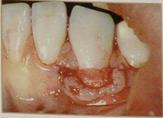

Суть этих методик в том, что между первичным лоскутом и поверхностью корня помещается второй слой – соединительная ткань, полученная, как правило, с области твердого неба (рис. 12). Давно установлено, что подлежащая под слизистой соединительная ткань является хорошим источником клеток для репопуляции эпителия и надежным источником для увеличения зоны кератинизированной десны. Забор аутотрансплантата проводится из зоны от первого моляра до резцов. В зависимости от вида получаемого трансплантата (с эпителиальной полоской или без) используются различные техники разреза. Существует целая классификация разрезов на твердом небе по Liu.

1.Langer и Langer (1985) – совмещение коронально перемещенного лоскута и соединительнотканного трансплантата. Препарирование расщепленного первичного лоскута включает в себя горизонтальные, вертикальные разрезы и деэпителизацию сосочков.